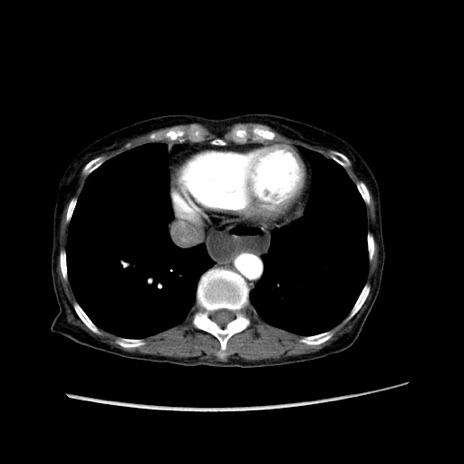

冠状断像